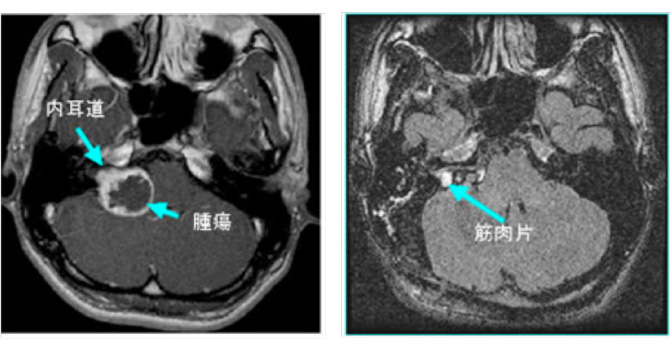

図4:神経繊維腫症2型の症例

42歳女性 両側の聴神経腫瘍をみとめる。NF2の症例。両側とも聴覚は良好であり、大きい方の腫瘍をまず摘出。聴覚は術後やや低下したが温存された。右の小型聴神経腫瘍は拡大傾向なく経過を観察している。

▲ 術前MRI

▲ 術後MRI 左側の腫瘍は被膜を残して摘出されている